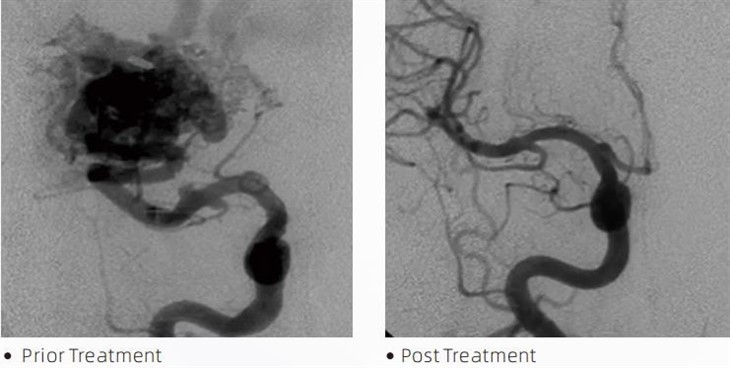

LavTMembolik yapıştırıcı, serebral anevrizmalar, arteriyovenöz malformasyonlar ve tümörler gibi durumları tedavi etmek için minimal invaziv prosedürler sırasında girişimsel nöroradyologlar tarafından kullanılan tıbbi bir cihazdır. Lava embolik yapıştırıcı güvenlik, kullanım kolaylığı ve etkinlik açısından hem tıp uzmanlarına hem de hastalara birçok fayda sunar. Lav, kan damarlarını hızlı ve verimli bir şekilde kapatabilir. İşlem, yapıştırıcının doğrudan anevrizmayı veya malformasyonu dolduran döküm benzeri bir kütle halinde polimerize olduğu ve sertleştiği hedeflenen damara enjekte edilmesini içerir. Daha sonra lezyona giden kan akışını etkili bir şekilde keserek, yırtılmasını önler ve kalıcı hasar veya felç riskini azaltır. Lav; Lav-12, Lav-18 ve Lav-34'ı içerir. Her formülasyon, belirli klinik ihtiyaçları karşılamak üzere tasarlanmıştır. Lava-18, genel kullanım için standart formülasyondur. Lav-34, yüksek akışlı kaplar için yüksek viskoziteli bir yapıştırıcıdır. Lava-12 daha düşük bir viskoziteye sahipken ve daha akıcı olduğundan uzak mikrodamarcıklara izin verir. Bu seçeneklerle, girişimsel nöroradyologlar en iyi sonuçları elde etmek için uygun Lava formülasyonlarını seçebilirler. Lava'nın en dikkat çekici özelliklerinden biri de yapışmama özelliğidir. Bu madde, hedeflenen bölgeye ulaşana kadar stabil kalması için özel olarak formüle edilmiştir. Bu özellik, Lava embolik yapıştırıcının arterin içine doğru bir şekilde yerleştirilebileceği ve çevreleyen dokuya yapışmadan veya bağlanmadan orada kalabileceği anlamına gelir.